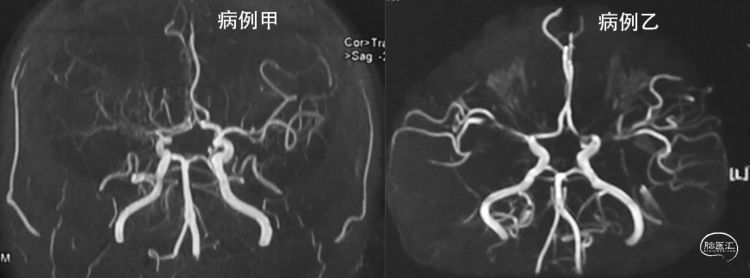

病人甲的影像资料:

MRA:右侧大脑前动脉、大脑中动脉闭塞,左侧大脑中动脉分支减少;

病人乙的影像资料:

MRA:双侧大脑中动脉、左侧大脑前动脉重度狭窄至闭塞

两个病例,都是年轻女性,没有确切严重的三高病史,都是比较符合双侧颈内动脉末端/大脑前/大脑中起始部受累的表现,相比较而言,病例乙的血管狭窄/闭塞双侧更对称一些,两个都是“烟雾病”的可能性大,病例乙可能性应该更大。